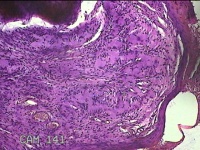

左示指肿物

性别

男

年龄

35岁

临床诊断

左示指末节肿物性质待查?

一般病史

发现左示指肿物

标本名称

大体所见

灰白暗红色肿物0.7x0.3x0.2cm一个,表面糜烂,切面灰白暗红色,质软。